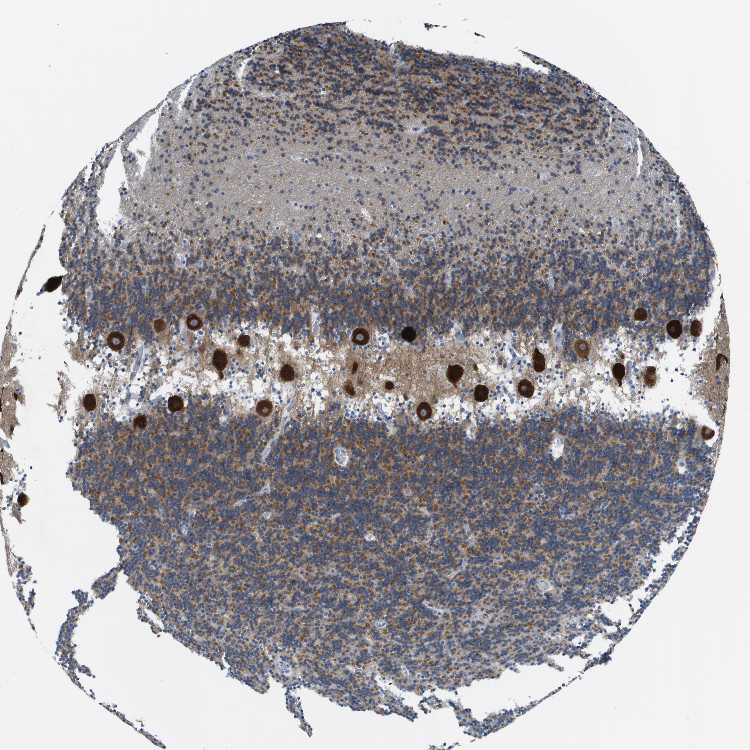

CEREBELLUM - Antibody stainingi

Antibody staining in the annotated cell types in the current human tissue is reported as not detected, low, medium, or high, based on conventional immunohistochemistry profiling in selected tissues. This score is based on the combination of the staining intensity and fraction of stained cells.

Each image is clickable and will lead to virtual microscopy that enables deeper exploration of all samples and also displays staining intensity scores, fraction scores and subcellular localization as well as patient and tissue information for each sample.

Antibody HPA019713Antibody CAB018587

Purkinje cells HighHigh

Cells in granular layer HighMedium

Cells in molecular layer MediumLow